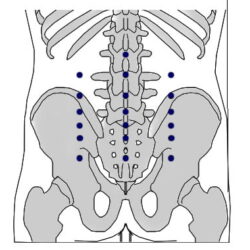

הסבר והדגמה של קריסטל המים 66.13 Shui jing

קריסטל המים 66.13 Shui jing היא נקודה חשובה באקופונקטורה של מאסטר טונג לטיפול בהפרעות גינקולוגיות, בוידאו אני מסביר אודות הנקודה ומדגים את בדרך לאתר ולדיקור.

הסבר והדגמה של קריסטל המים 66.13 Shui jing קרא עוד »